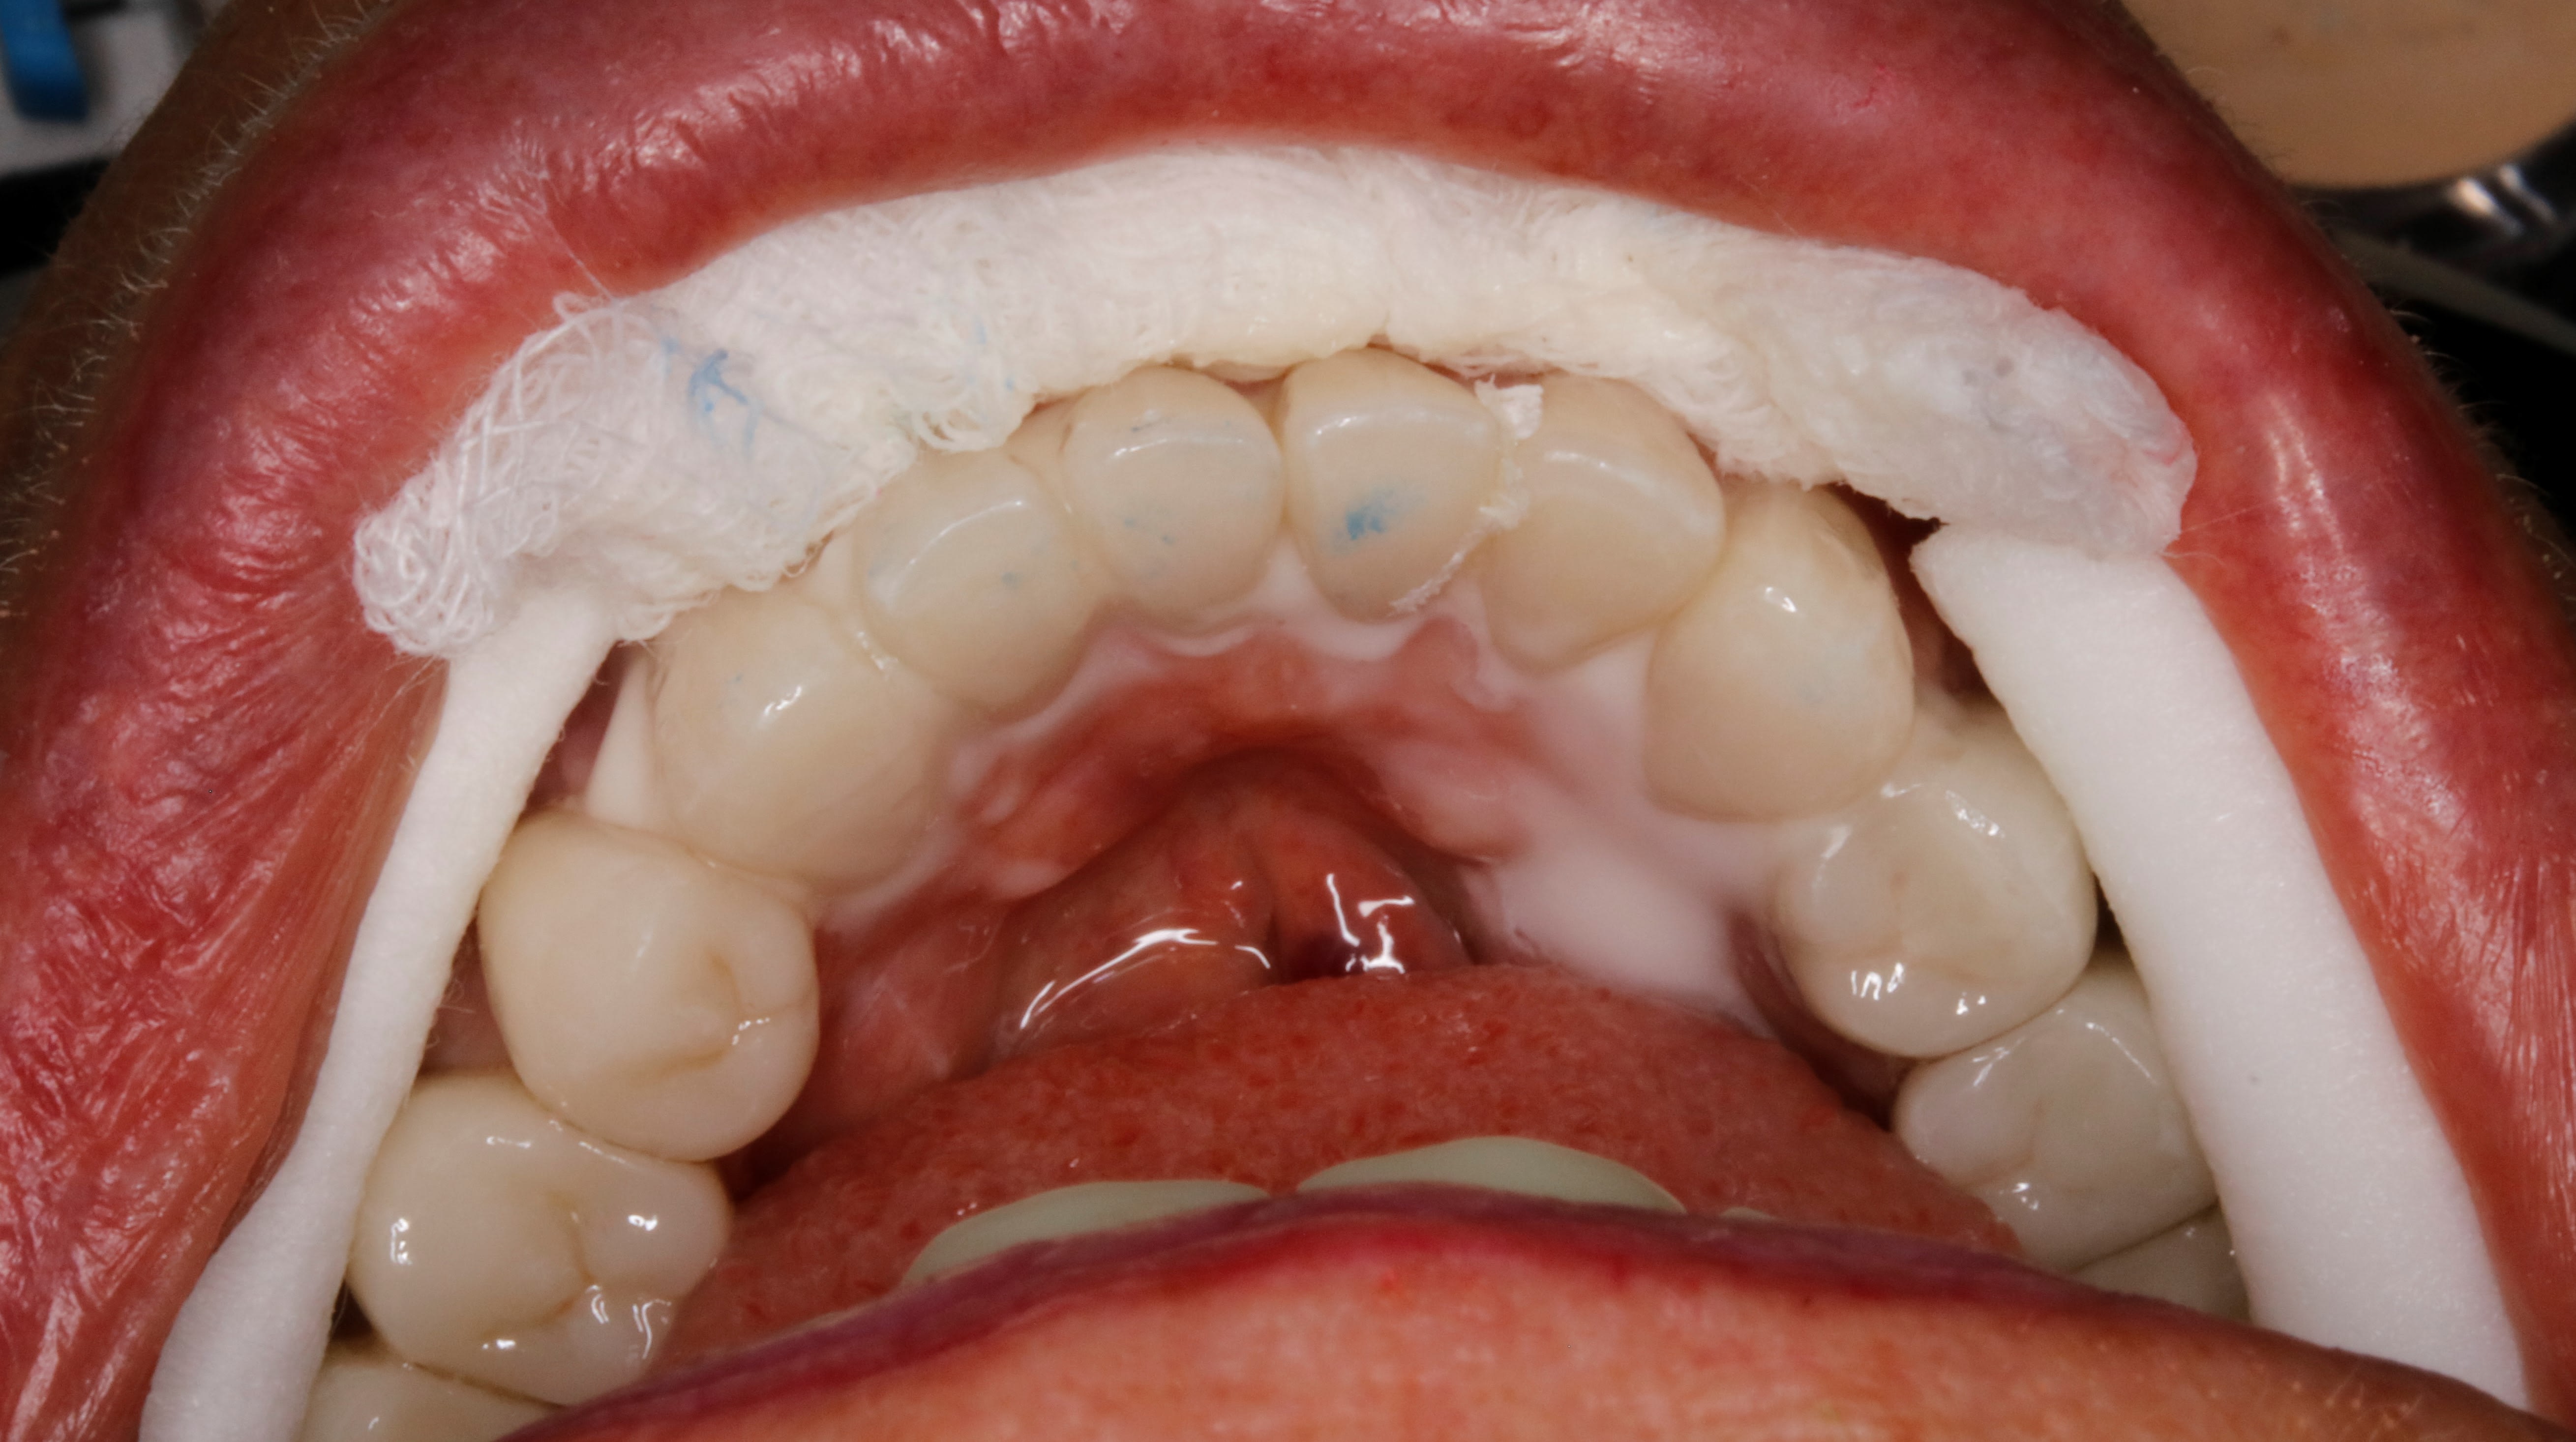

je reviens sur mes mousses avec un cas de ce matin .

autant pour un inlay , tu peux utiliser un bâton , mais quand tu commences à faire des prothèses à la demi douzaine , 6 bâtons ça commence à faire un peu mikado cette affaire .

eh oui parce que une fois l essayage fait , gentiment sans trop enfoncer , rien ne ressemble plus à une 31 qu une 41 ,... surtout lorsque toutes les tailles sont identiques en forme . et puis à attraper , c est tout petit , conique , et ça glisse à mort .

alors au moment ou tu scelles , une fois que tu farcis , tu ne vois plus rien , tu risques de te tromper de dent ( ça m est arrivé ) , de les faire tomber , de les mettre à l envers .etc

alors pour ne pas te tromper , surtout si tu ne les scelles pas en même temps genre 1 sur 2 ( pour mieux gérer les points de contacts ) . ,

la mousse prend tout son intérêt / aux bâtons . moins de stress le scellement .

merci . voila ,avant et pendant

maintenant faut lui faire pareil en haut ;-)

Oui , Perle , c est prevu .

Pour pouvoir faire un haut esthétique et fonctionnel , il faut tjs commencer par le bas sinon tu te mets vite dans une impasse .